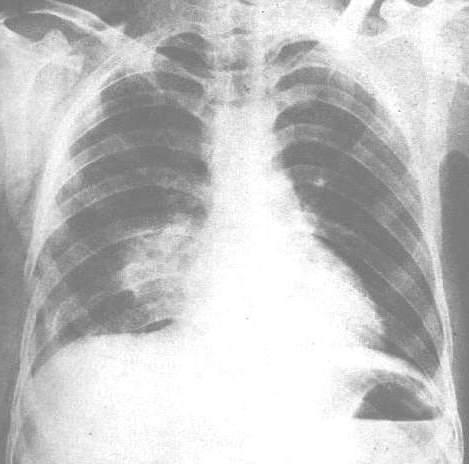

肺挫傷(はいざしょう Lung Contusion)は、胸部の傷害により引き起こされる肺の外傷である。

肺挫傷は、鈍的外力が直接作用することによって引き起こされるが、外傷に関連する爆傷および衝撃波が原因で引き起こされる場合がある。世界大戦における爆薬の使用で、爆破から肺挫傷を生じたため、認知度を高めた。また、交通外傷により同様の衝撃が引き起こされるが、シートベルトとエアバッグを使用することで、危険を減らすことができる。